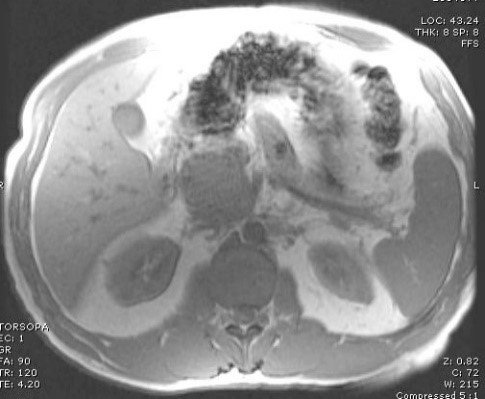

- Kontrastlı KT və ya MRT standart müayinədir, şişi və yayılma dərəcəsini müəyyənləşdirilməsində önəmlidir.

- Görüntüləmdə: erkən arterial fazada contrast tutan və venoz fazada yuyulan, MRT-də hipointens, ətraf toxumalara invaziv, böyüməyə meylli, baş nahiyyəsində yerləşərək xoledoxu və pankreatik axacağı genişləndirən (“iki axacaq simptomu”) törəmə

- Kontrastlı KT/MRT (5 mm-lik kəsiklərlə aparılan kontrastlı KT/MRT 50 – 60% həssaslıq göstərir.